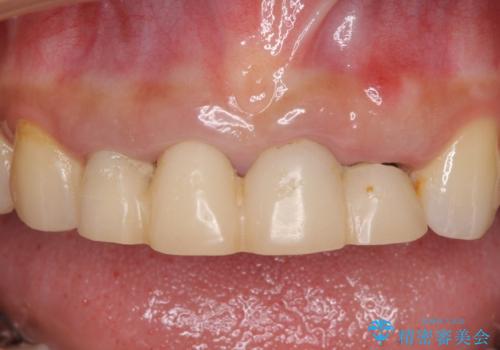

- 地元の歯科医院にて前歯4歯を仮歯に替えたものの、汚れていることが気になるとのことで来院された患者様です。

不適な仮歯の影響で歯肉が腫れていたため、新しい仮歯に替えた後に歯肉の腫れが引くのを待ち、オールセラミッククラウンにて補綴することとしました。

根尖病変が原因で、膿が出てきている歯があったため、仮歯を置き換える際に根管治療を行うこととしました。

仮歯を変えたことで歯肉の腫れは引き、根管治療も功を奏して膿の出口はきれいに消退しました。